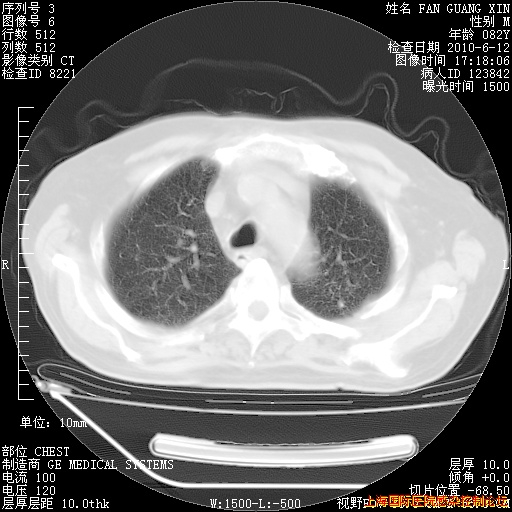

补发6月12日肺部CT肺窗

6月12日肺窗